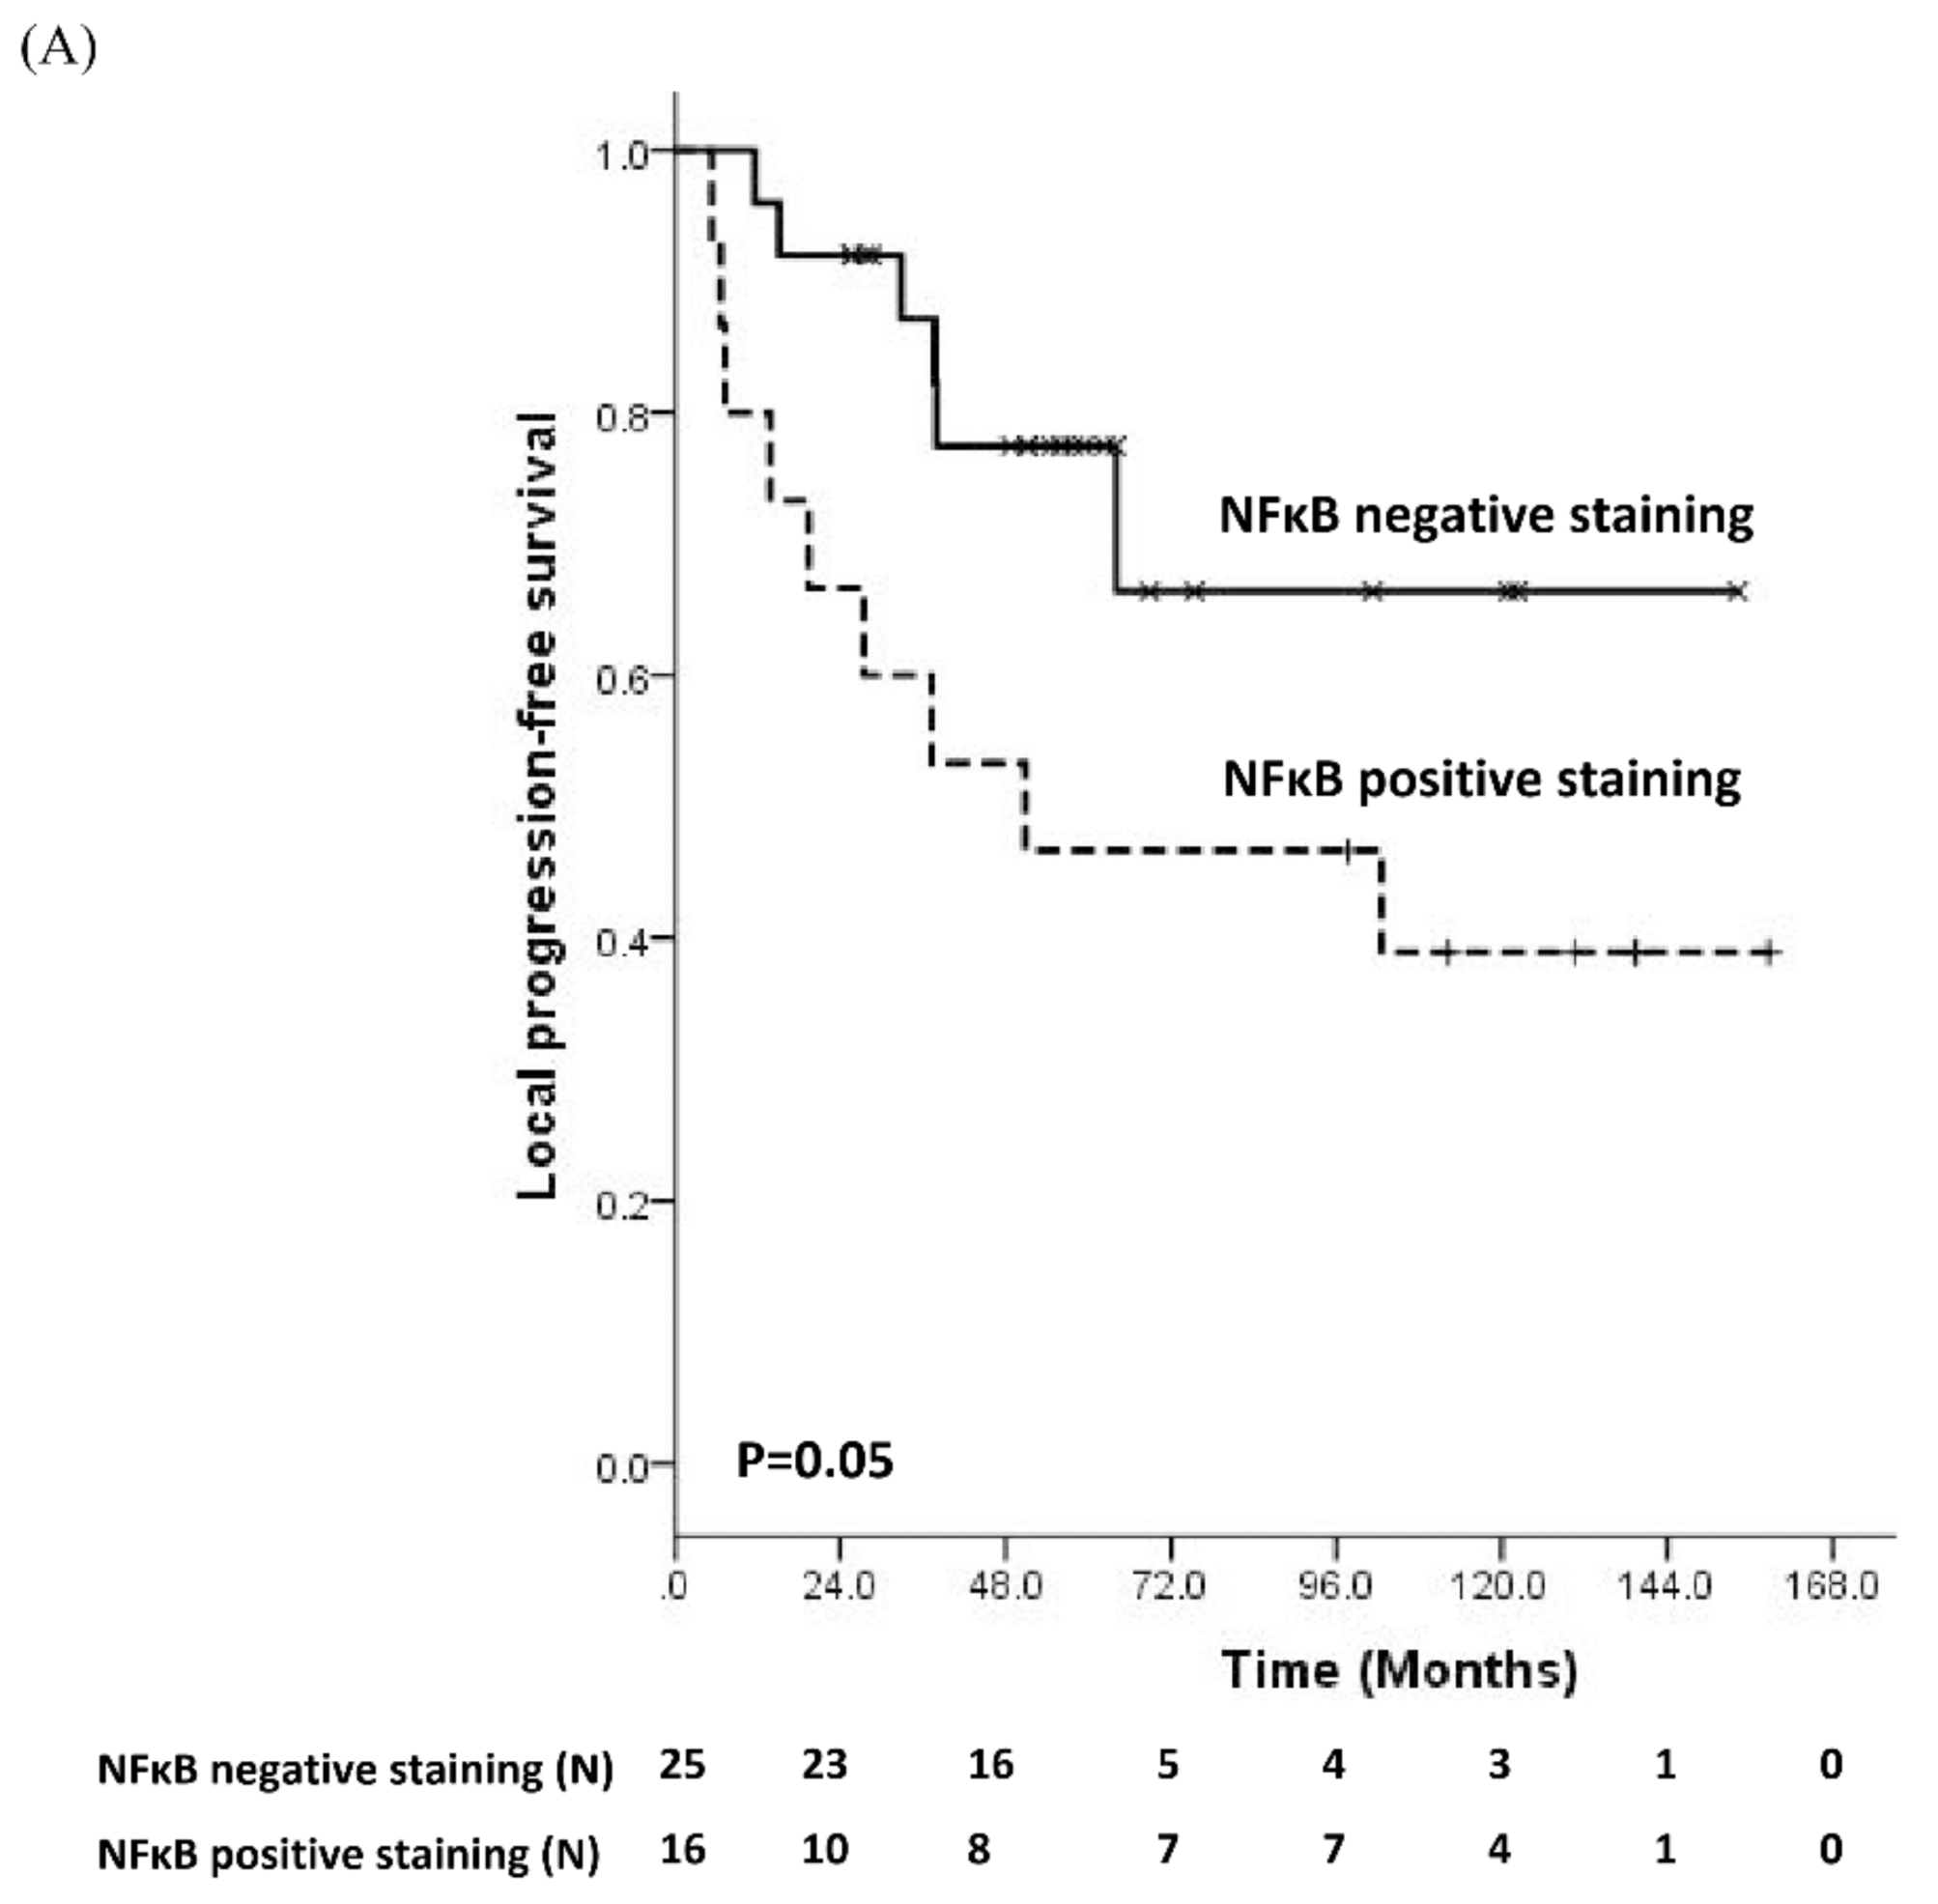

3.2. Prognostic Significance of Molecular Biomarker

3.3. Comparisons of Immunostaining of NFκB between Pre-Treatment Samples and Recurrent Samples